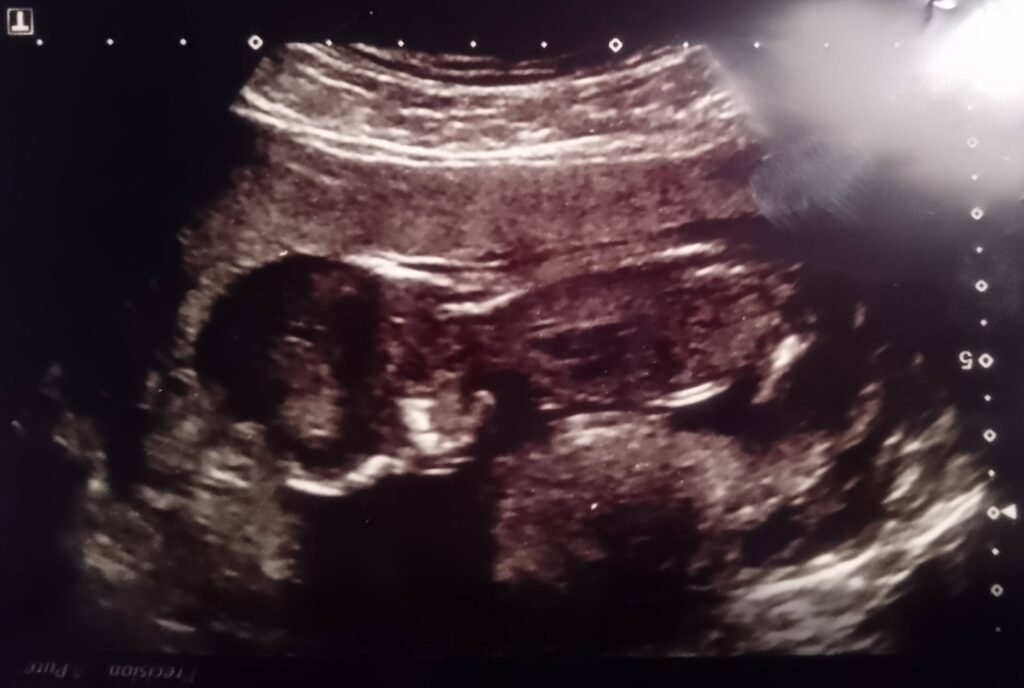

Years later, while reviewing my own archived ultrasound scans, I found what had been missed – or unacknowledged – in real time:

A clear bicornuate or septate uterus.

Across multiple NHS scans, the uterine contour is visibly divided, with implantation restricted to one horn and a second chamber vacant.

The images here show a pregnancy confined to one horn – the other visibly empty.

This is common in bicornuate and septate uteruses, yet rarely acknowledged unless complications arise.